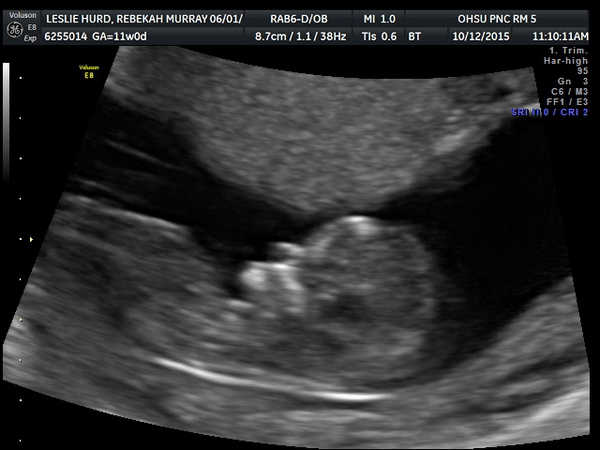

11 Week Ultrasound

Monday 12 October 2015